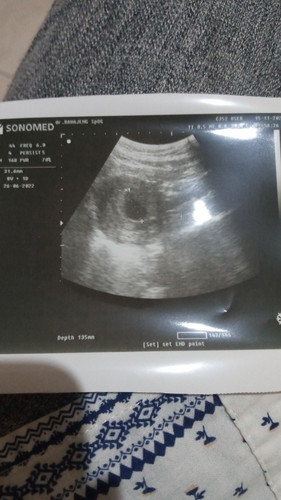

#firstbaby #pleasehelp halo bun mau tanya... aku hamil udah masuk w10, tp usg sama dokter bilang size nya kyk umur 8w, nah sejak 3-4 hari lalu pendarahan dikit sama kluar jaringan gitu, kadang nyeri ringan kadang gak, udah d kasik obat penguat rahim tp efek nya aku jd sakit gigi, pdhal seumur2 belum pernah sakit gigi dokter bilang 2 minggu lg suruh cek kontrol, tp kalo keadaan gini sebelum 2 minggu apa gpp periksa lg bun? jujur aku takut sama kepikiran :( takut adek kenapa2